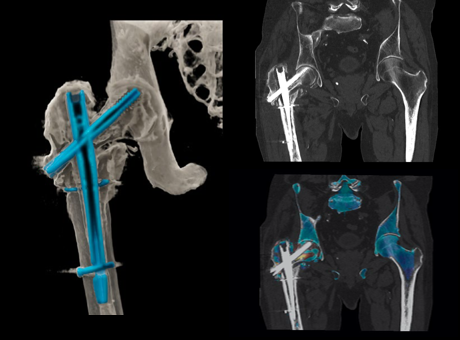

다음과 같은 검사가 가능합니다.

* 이해를 돕기 위한 이미지이며, 실제 촬영 시 이와 상이할 수 있습니다.